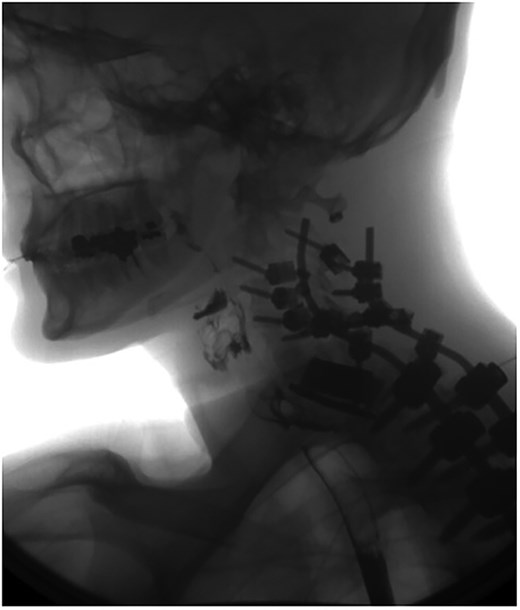

A 35-year-old male presented with a month-long history of dysphagia, severe headache, and posterior neck pain that radiated to the occiput. His medical history was significant for cervical surgeries, including an anterior cervical discectomy and fusion (ACDF) at C5/C6 one year and two months ago (Fig. 1). Shortly thereafter, the patient underwent revision surgery along with posterior plating from C5 to T1 due to osteomyelitis, worsening cervical deformity, and retropharyngeal abscess (Fig. 2). Initial workup included a noncontract computed tomography (CT), demonstrating increased gas density at C6 corpectomy site and post cricoid region (Fig. 3). A swallow study was obtained based on suspicion of a perforation and demonstrated extraluminal leakage of contrast posteriorly at the C6 level, consistent with initial CT (Fig. 4). Surgery included removal of the anterior and posterior hardware and esophageal repair. Although initially the esophageal injury was suspected to be related to the hardware, intraoperatively, it was found the instrumentation was not in communication with the esophagus. This confirmed the perforation was unrelated to direct injury from the cervical hardware construct, which was intact. The esophagus was repaired with a pectoralis flap. The postoperative course was uneventful, and the patient was discharged home after one week. The patient later died due to severe complications of substance abuse unrelated to the operation.

Swallow study demonstrating extraluminal leakage of contrast posteriorly at the C6 level consistent with CT findings.